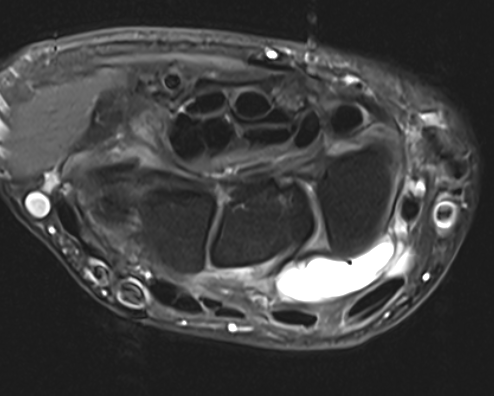

MRI

Dorsal ganglion

Dorsal ganglion arising from scapholunate joint

Dorsal ganglion arising from scapho-lunate joint